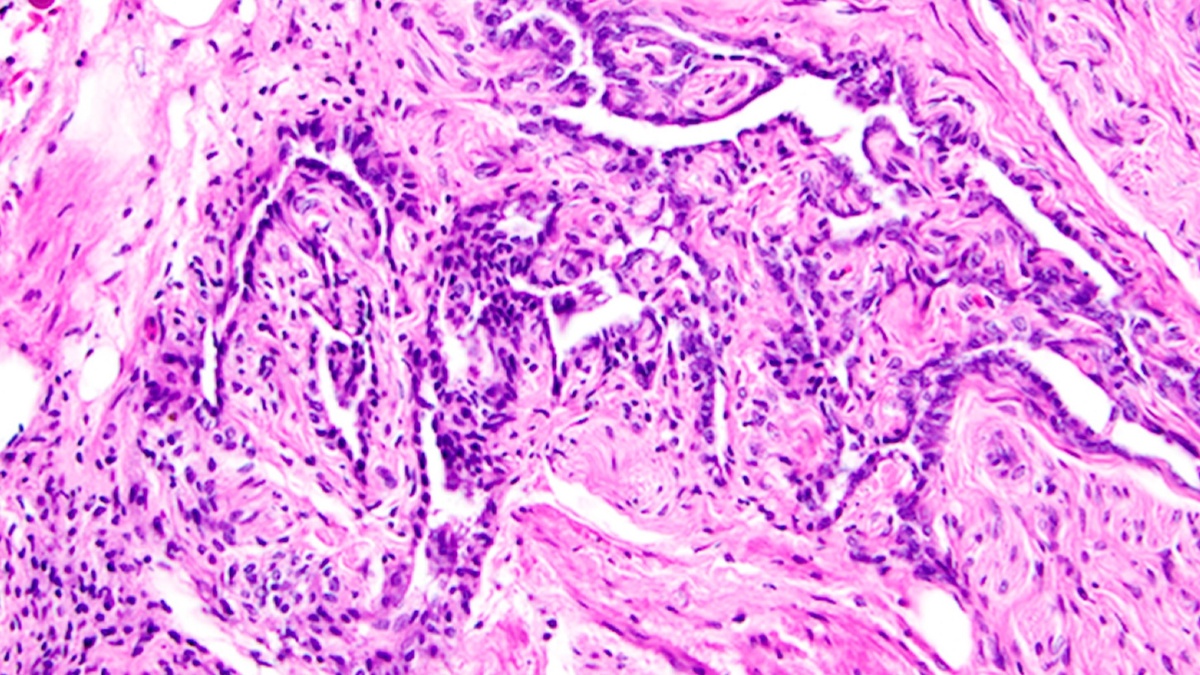

Структура, известная как rete ovarii (РО), более века считалась бесполезным рудиментом. Однако новое исследование на мышах показало, что этот орган может играть критическую роль в работе яичников и фертильности. Открытие, опубликованное в журнале eLife, переворачивает представление о женской репродуктивной системе. Открытие, которое игнорировали 150 лет РО впервые обнаружили у человека в 1870 году, но тогда ученые сочли его эволюционным пережитком — подобно аппендиксу или зубам мудрости. Современные технологии, включая масс-спектрометрию и флуоресцентную визуализацию, позволили доказать, что этот орган вовсе не бесполезен. "Женский репродуктивный тракт традиционно описывают как вульву, влагалище, шейку матки, матку, яйцеводы и яичники. Мы предлагаем добавить в этот список РО и исследовать его как важный компонент репродуктивной функции." Три зоны rete ovarii и их функции Исследователи выявили три анатомически и функционально разных участка РО: Эксперименты с флуоресцентным красителем п

Структура, известная как rete ovarii (РО), более века считалась бесполезным рудиментом. Однако новое исследование на мышах показало, что этот орган может играть критическую роль в работе яичников и фертильности. Открытие, опубликованное в журнале eLife, переворачивает представление о женской репродуктивной системе.

РО впервые обнаружили у человека в 1870 году, но тогда ученые сочли его эволюционным пережитком — подобно аппендиксу или зубам мудрости. Современные технологии, включая масс-спектрометрию и флуоресцентную визуализацию, позволили доказать, что этот орган вовсе не бесполезен.